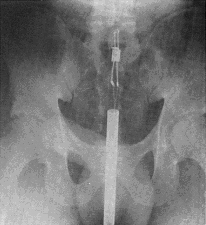

Last Thursday, a load of lycra-clad Bawwstonians got pwned by terrorists at some gay marathon. Loads of people got their legs blown off and shit. Some argue however, that it shouldn't have spoiled the day - first it was a marathon, now it's a three-legged race.